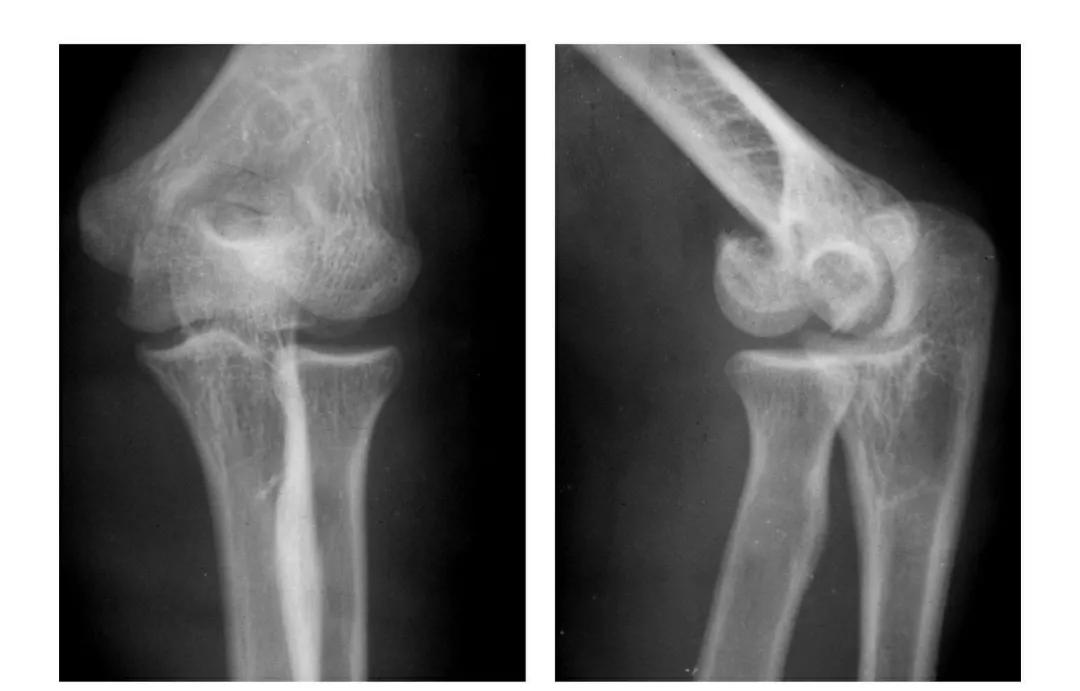

肱骨小头冠状面骨折

(一)完全骨折

本病亦称哈-斯(Hahn-Steinthal)型骨折

例1:肱骨小头基底部呈冠状面骨折,骨折块呈半球状向肘前上方移位。

例2:肱骨小头基底部冠状面骨折,骨折块呈半球状向肘前移位并肱骨内上髁无移位骨折。